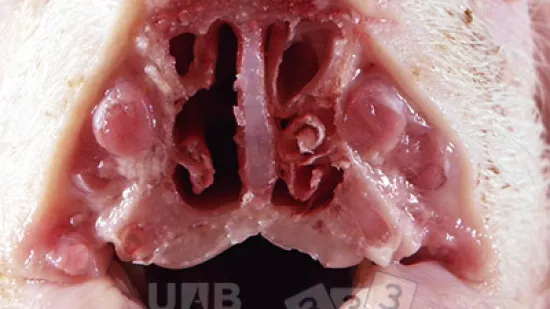

Semaine du 25-Jul-2022

Quelle est la lésion rencontrée en sectionnant la cavité nasale d’un porc de 10 semaines d’âge ?